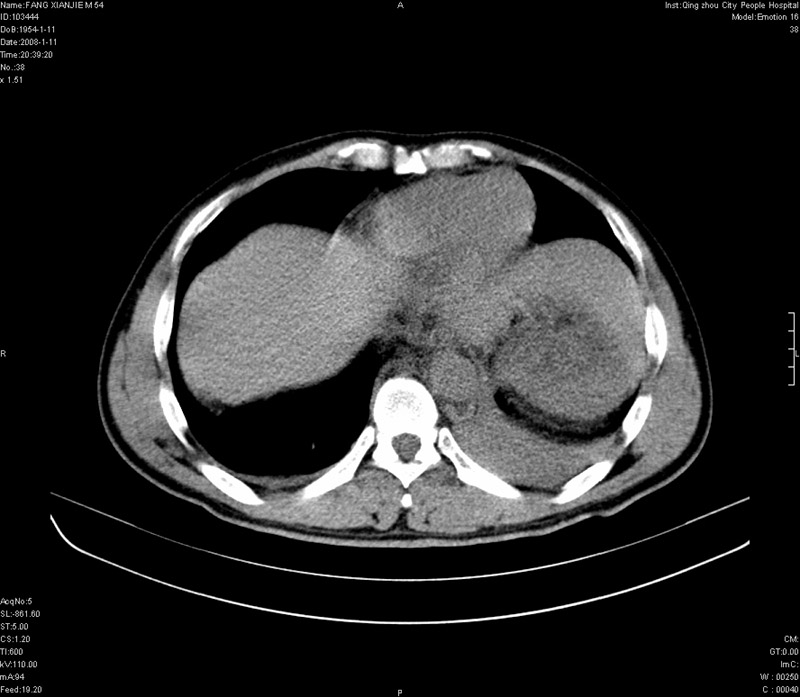

男性,40岁。胸部被车压伤伴胸痛1小时来院就诊。检查:一般情况尚可,血压110/80,胸部及上腹部压痛。结果在三天后公布。骨窗在横断位、冠矢状显示肋骨、胸椎、和胸骨未见骨折征象。

ct11308:胸部外伤1小时(证实病例) (2008-1-13 16:2)结果如下:病人入院后两小时后症状加重,8小时后在征得病人家属同意做了ct增强扫描。如下图。最终临床诊断:外伤性胸主动脉破裂并纵隔内血肿。由于有运动性伪影,胸骨在矢状面重建的图像似有骨折征,这是一种假象,我们称之为“假骨折”,这在多层ct重建中经常性遇到,必要时要结合横断图像鉴别之。现在,病人的一般情况较差,是否要手术家属尚有争议,如果手术修补,难度较大,需要专门预定制作固定支架。

当然,对于该病例,其它非重要的诊断还有:右侧少量气胸;左侧胸腔积液;左侧轻度肺挫裂伤。对于纵隔内血肿,我们曾经遇到过多例,也有怀疑主动脉的破裂,但是,均未得到具体出血部位的明确诊断。